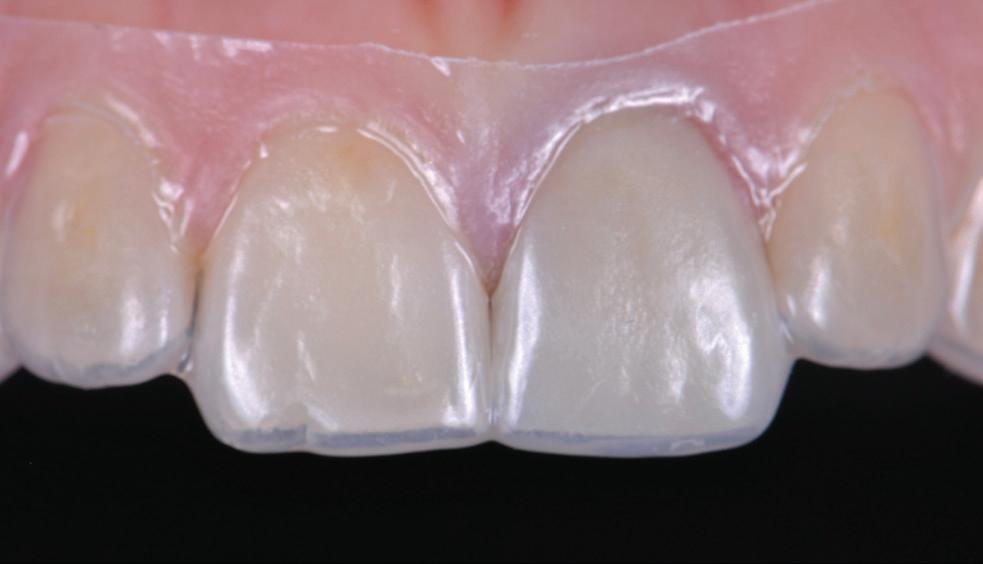

protection from needle stick injuries

security

for the patient

Transparent